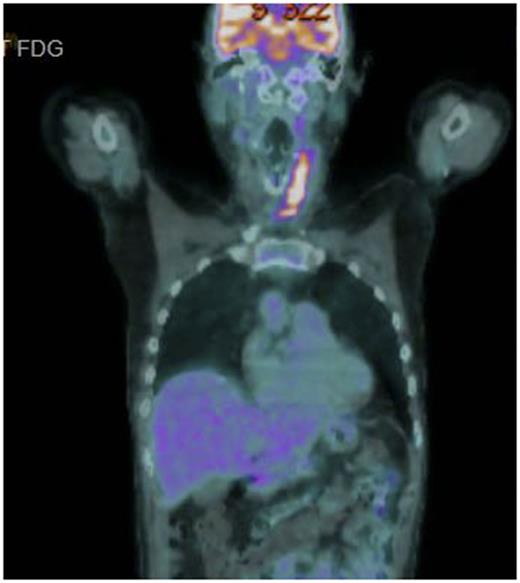

A 56 year old male presented with rapid onset superior vena cava obstruction that caused an intensive care admission at the time of diagnosis. Staging showed stage 2 with neck disease, near complete SVC obstruction and a 6 x 5 x 5cm superior mediastinal mass. Therapy was commenced with R CODOX-M / R IVAC with an initial symptomatic improvement but by the time of recovery from course 2, the symptoms of respiratory distress were recurring in the left neck where partial acute respiratory obstruction occurred. No significant improvement in the neck mass was seen on repeat CT and urgent radiotherapy (R/T) was given to relieve symptoms. Persistent active disease was then confirmed by CT /PET scanning in the left neck (SUV 10.8), an exemplar image of this scan is shown in Figure. The patient was counselled as to the dire prognosis but was unwilling to accept that further intensive treatment was unlikely be successful and requested further chemotherapy. In the light the intensity of the treatment already delivered a novel strategy was conceived and agreed.

End of treatment PET showed a complete response which has now been maintained for 12 months. Two attempts at stem cell mobilisation failed, despite the use of plerixifor, so a consolidation autologous stem cell transplant was not pursued. End of treatment radiotherapy to sites of initial disease was implemented after end of treatment restaging.